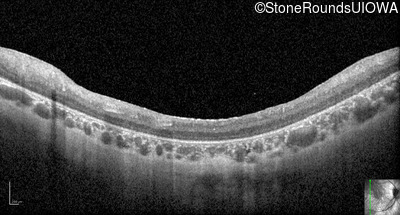

Optical Coherence Tomography - Right - 10/300 sc

Exemplar / OCT Stack